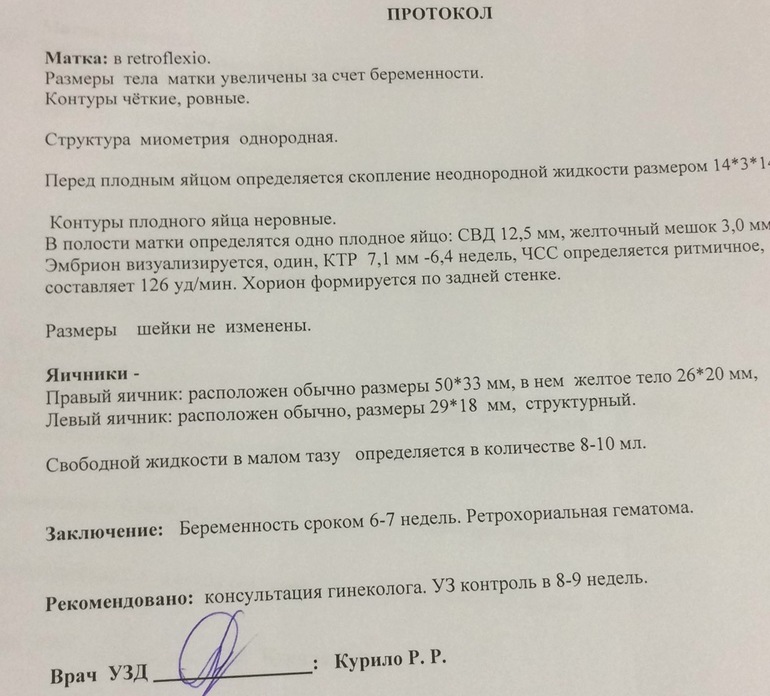

В общем...фуууух) выдохнула)сроку соответствует.

Есть гематома, пя немного кривовато, матка в загибе...будем наблюдать.